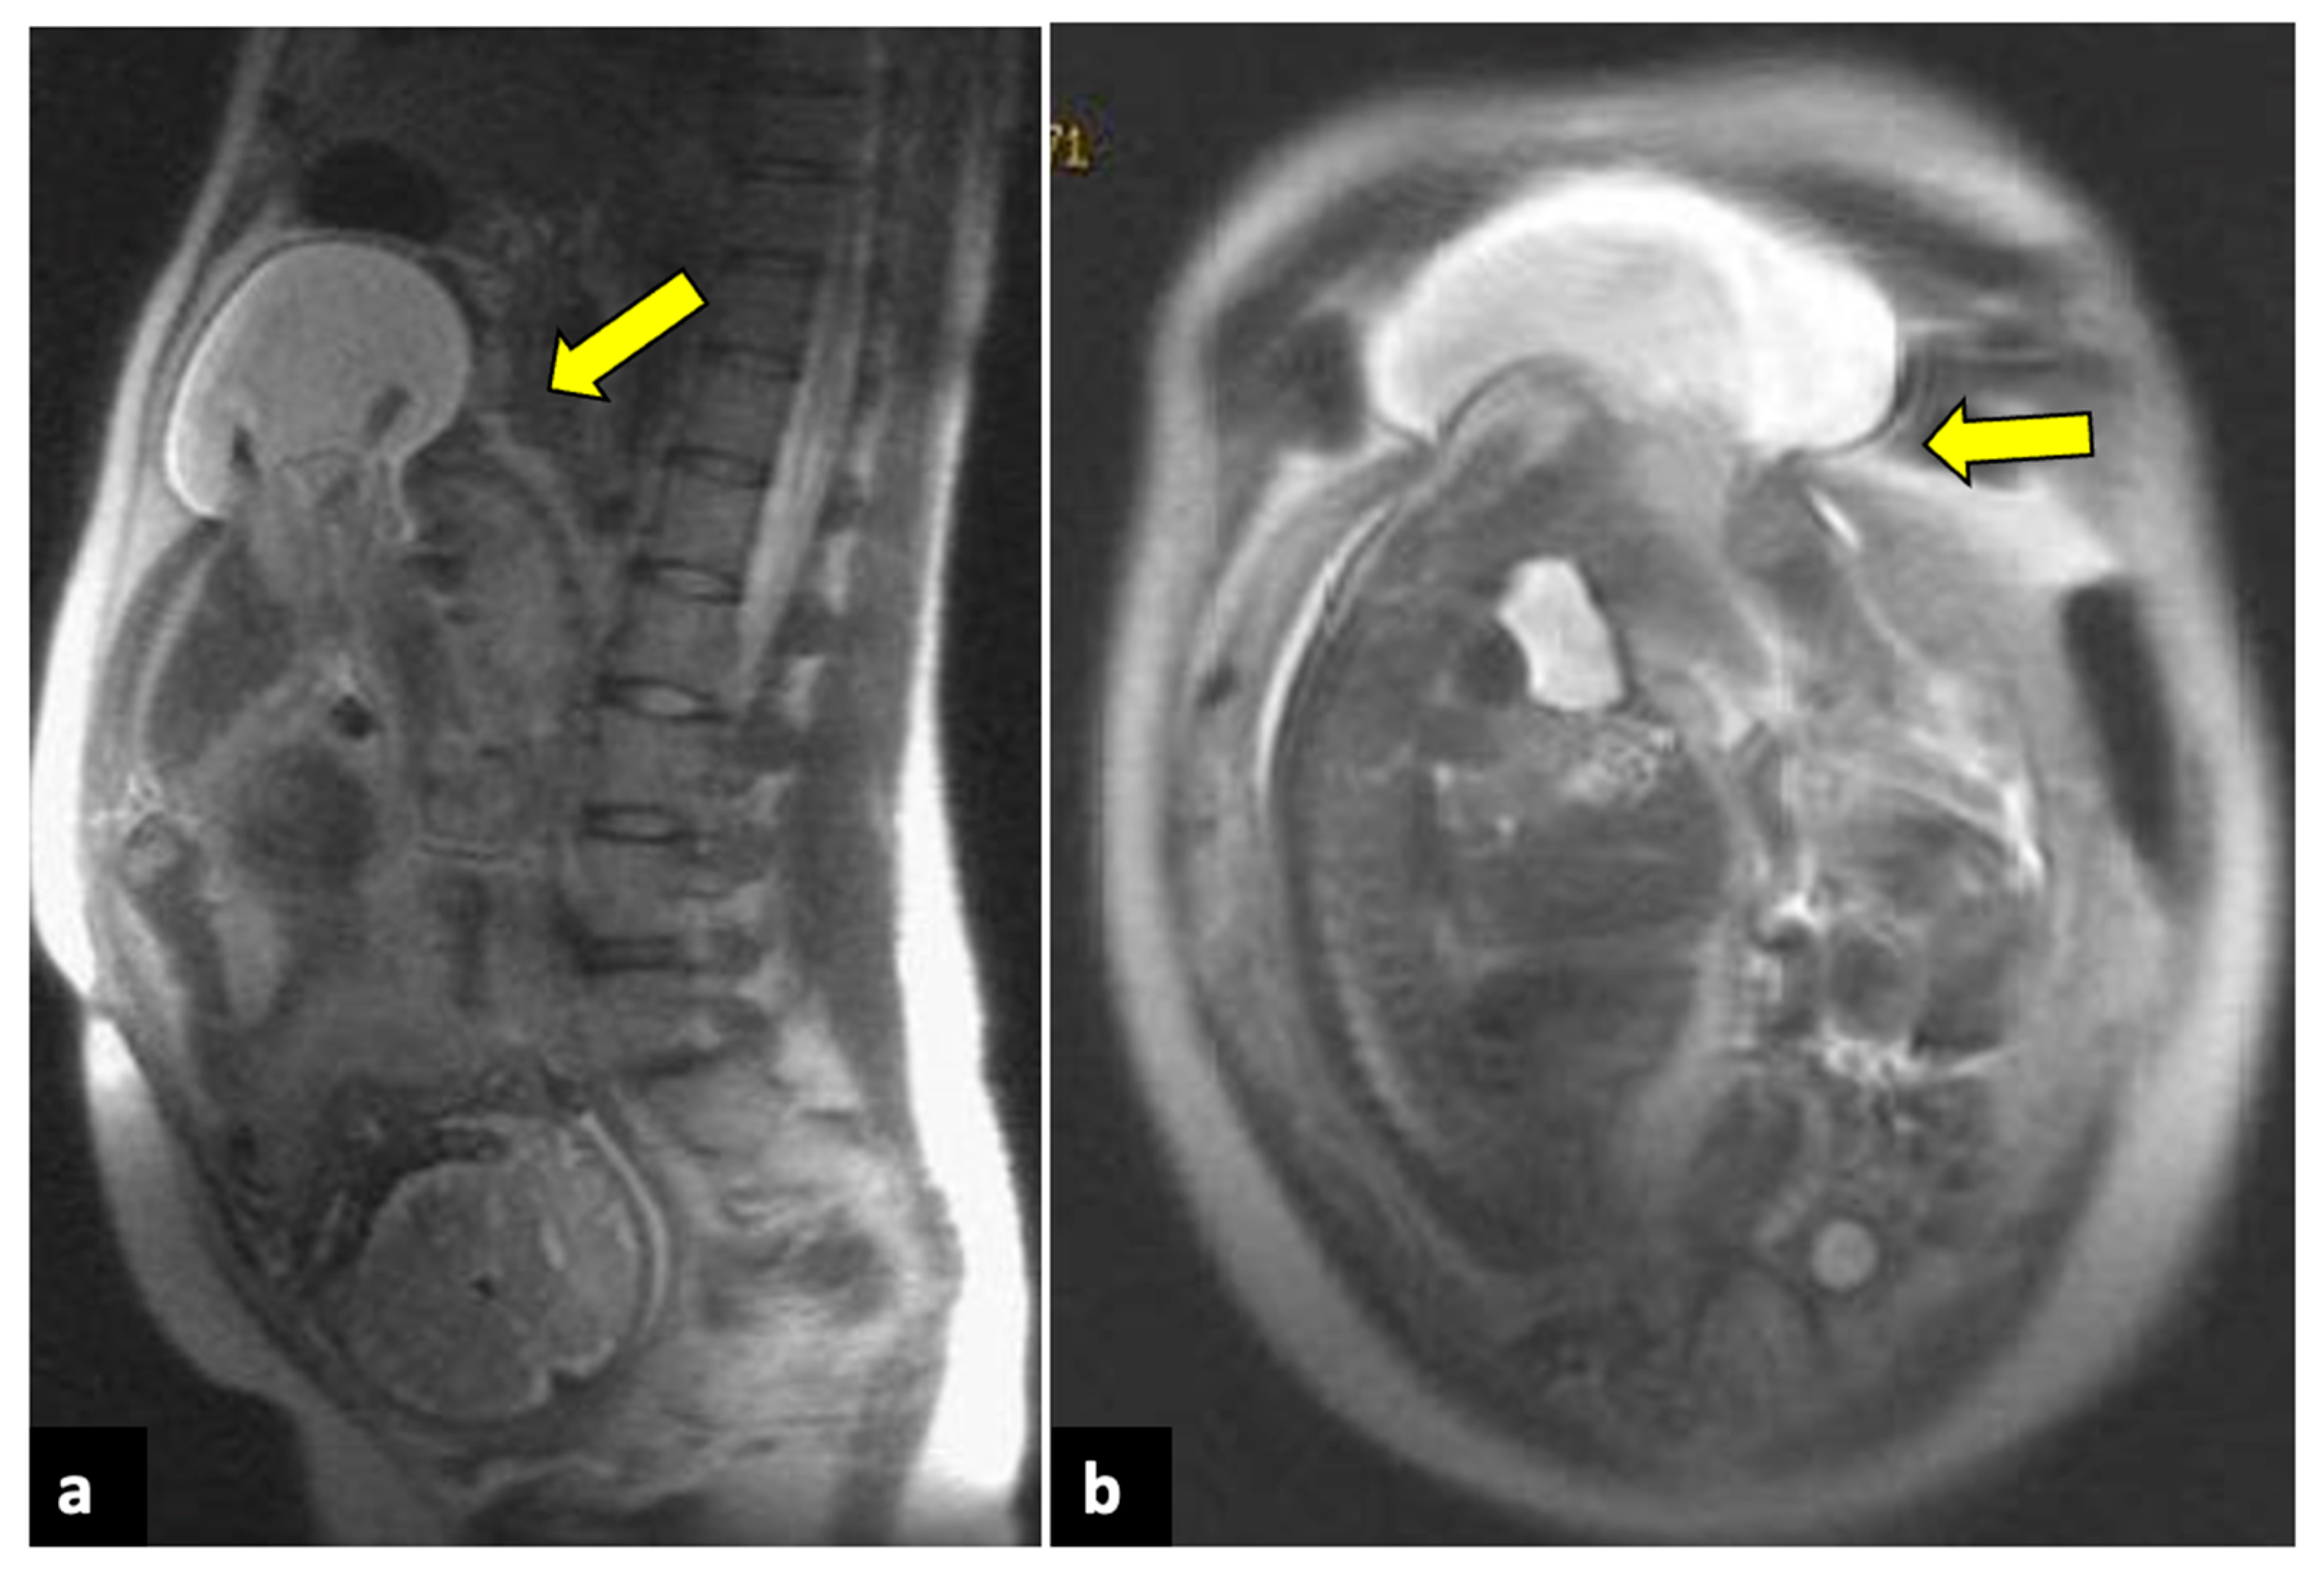

2.9. Ectopic Pregnancy

- Mullany, K.; Minneci, M.; Monjazeb, R.; Coiado, O.C. Overview of ectopic pregnancy diagnosis, management, and innovation. Womens Health 2023, 19, 17455057231160349. [Google Scholar] [CrossRef] [PubMed]

- George, R.; Powers, E.; Gunby, R. Abdominal Ectopic Pregnancy. In Baylor University Medical Center Proceedings; Taylor & Francis: Abingdon-on-Thames, UK, 2021; Volume 34, pp. 530–531. [Google Scholar] [CrossRef]

- Ramanathan, S.; Raghu, V.; Ladumor, S.B.; Nagadi, A.N.; Palaniappan, Y.; Dogra, V.; Schieda, N. Magnetic Resonance Imaging of Common, Uncommon, and Rare Implantation Sites in Ectopic Pregnancy. Abdom. Radiol. 2018, 43, 3425–3435. [Google Scholar] [CrossRef] [PubMed]

- Hendriks, E.; Rosenberg, R.; Prine, L. Ectopic Pregnancy: Diagnosis and Management. Am. Fam. Physician 2020, 101, 599–606. [Google Scholar]

- Furey, E.A.; Bailey, A.A.; Pedrosa, I. Magnetic Resonance Imaging of Acute Abdominal and Pelvic Pain in Pregnancy. Top. Magn. Reson. Imaging 2014, 23, 225–242. [Google Scholar] [CrossRef]

- Kao, L.Y.; Scheinfeld, M.H.; Chernyak, V.; Rozenblit, A.M.; Oh, S.; Dym, R.J. Beyond Ultrasound: CT and MRI of Ectopic Pregnancy. AJR Am. J. Roentgenol. 2014, 202, 904–911. [Google Scholar] [CrossRef]

- Srisajjakul, S.; Prapaisilp, P.; Bangchokdee, S. Magnetic Resonance Imaging in Tubal and Non-Tubal Ectopic Pregnancy. Eur. J. Radiol. 2017, 93, 76–89. [Google Scholar] [CrossRef]